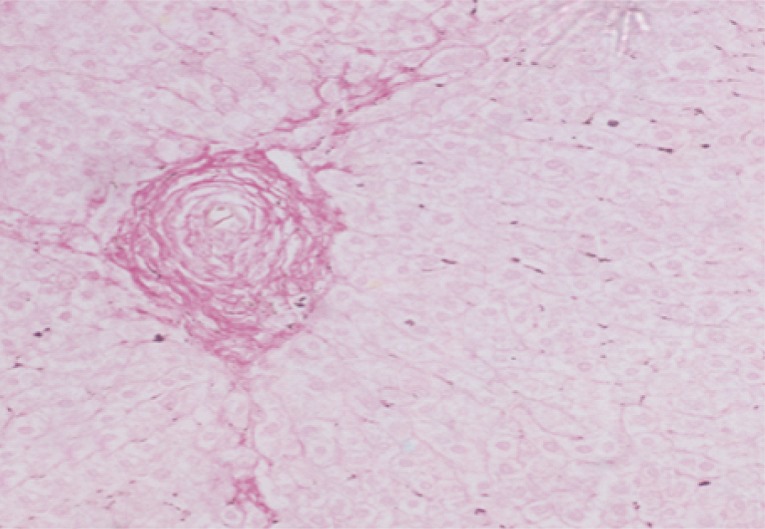

Sirius red staining for collagen

The collagen content of the liver sections stained with Picrosirius red was evaluated quantitatively for the percentage areas of collagen using Computerized Cell Image Analysis. Collagen fibers within the squares of the ocular reticule were counted at ×200 magnification [24].

Collagen content as determined by morphometric image analysis

Morphometric studies using Sirius red staining showed significant decreases in the fibrous tissue in BMSCs and BMSCs-HGF-treated groups compared to the infected control group (Figs. 6,7,8,9,10,11,12,13,14,15).

In our study, the extent of fibrosis was estimated by the quantitative morphometric analysis of the collagen content in Sirius red stained liver sections. The results revealed significant decreases in the collagen content after treatment with BMSCs alone or in combination with HGF. In this regard, Ghanem et al. [8] demonstrated that fibrosis developed during the chronic phase of granulomatous inflammation in murine schistosomiasis and it represented a protective function during infection by neutralization and sequencing egg antigens that can potentially damage host tissues. The inhibitory effect of inoculated BMSCs on the collagen deposition may be related to an enhancement of fibrotic degradation rather than a decrease in fibrosis synthesis.

Pretreatment with MSCs [30] significantly reduced liver fibrosis compared to untreated cells. Antifibrotic effects of MSCs have been previously documented by many authors [31,32], and this might have a contributing factor for the observed decline in the liver fibrosis. A significant reduction of collagen content [13] estimated by Sirius red staining in MSCs infusion group was recorded as compared to the PI control values. They [13] also reported that resorption of fibrous tissues was observed from the first month post BMSCs administration. This was more rapid than fibrous tissue resorption observed with anti-Schistosoma drug treatment, where resorption started 3 months after the treatment.